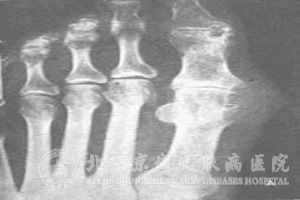

痛风的X线检查包括哪些?我们知道关节炎是痛风的主要表现症状,而对于人体骨骼的病变,一般使用肉眼很难观测,要通过医学仪器进行内部检测,也就是X射线检测。由于我们对医学治疗了解不多,所以不清楚痛风的X线检查包括哪些项目。

北京京城皮肤医院指出:痛风的X线检查包括常规检查和特殊检查。常规检查应摄取检查部位的正侧位片,骨骼病变摄片范围应包含一个相邻的关节。特殊检查主要有放大摄影、体层摄影和软组织钼靶摄影。放大摄影系利用小焦点的X线束自焦点向远处不断扩大的原理,使检查部位与胶片或X线感应板之间保持较大距离,从而获得放大图像,以便 地观察骨骼的细微结构。